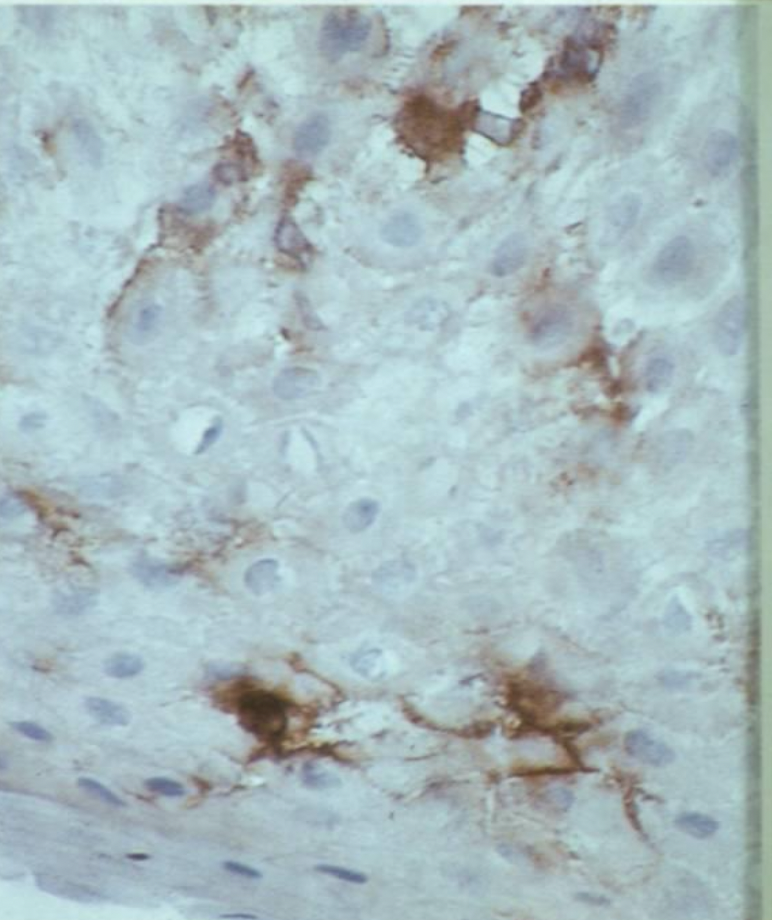

Langerhans’ Cells in epidermis, labeled brown